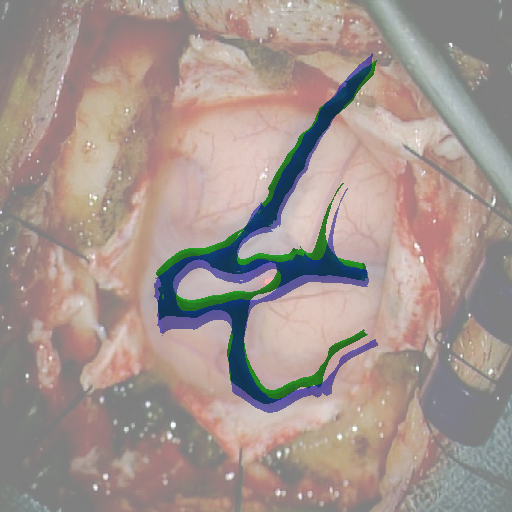

We tested our method retrospectively on 6 clinical datasets from 6 patients (cases) (see Fig. 5). These consisted of preoperative T1 contrast MRI scans and intraoperative images of the brain surface after dura opening. Cortical vessels around the tumors were segmented and triangulated to generate 3D meshes using 3D Slicer. We generated 100 poses for each 3D mesh (i.e.: each case) and used a total of 15 unique textures from human brain surfaces (different from our 6 clinical datasets) for synthesis using . In order to account for potential intraoperative brain deformations [4] we augment the textured projection with elastic deformation [21] resulting in approximately 1500 images per case. The surgical images of the brain (left image of the stereoscopic camera) were acquired with a Carl Zeiss surgical microscope. The ground-truth poses were obtained by manually aligning the 3D meshes on their corresponding images.

Test and Comparison on Clinical Images

We compared our method (Ours) with segmentation-based methods (ProbSEG) and (BinSEG) [7]. These methods use learning-based models to extract binary images and probability maps of cortical vessels to drive the registration. We report in Tab. 1 the distances between the ground truth and estimated poses. Our method outperformed ProbSEG and BinSEG with an average ADD error of mm compared to mm and mm, respectively. Our errors remain below clinically measured neuronavigation errors reported in [4], in which a mm average initial registration error was measured in 15 craniotomy cases using intraoperative ultrasound. Our method outperformed ProbSEG in 5 cases out of 6 and BinSEG in all cases and remained within the clinically measured errors without the need to segment cortical vessels or select landmarks from the intraoperative image. Our method also showed fast intraoperative computation times. It required an average of only milliseconds to predict the pose (tested on research code on a laptop with NVidia GeForce GTX 1070 8GB without any specific optimization), suggesting a potential use for real-time temporal tracking.

Fig. 5 shows our results as Augmented Reality views with bounding boxes and overlaid meshes. Our method produced visually consistent alignments for all 6 clinical cases without the need for initial registration. Because our current method does not account for brain-shift deformation, our method produced some misalignment errors. However, in all cases, our predictions are similar to the ground truth.